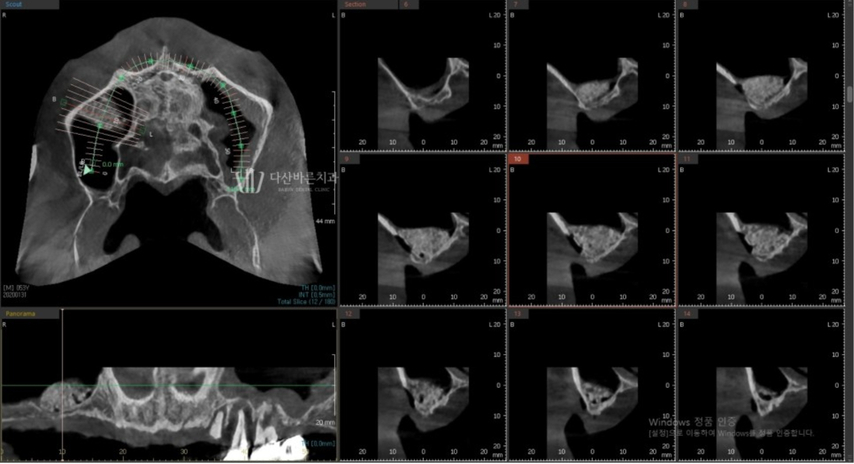

CT 3D cắt lớp (Nguồn: 3di)

Trên đây là ảnh chụp CT 3D cắt lớp giúp phân tích tình trạng xương nướu của bệnh nhân,

vị trí dây thần kinh,… và chuyển thành dữ liệu.